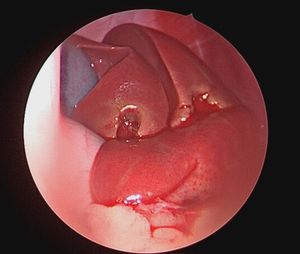

Treating the condition requires an understanding of this common reproductive emergency